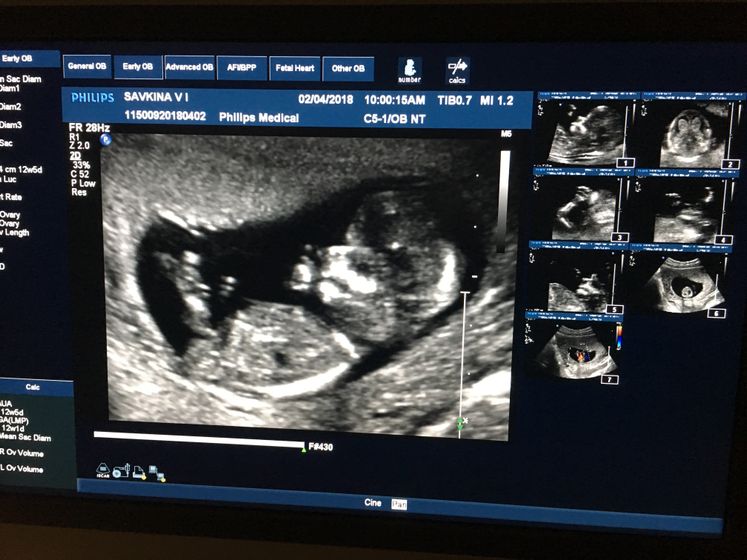

Сегодня наш первый скрининг ??? сказали что все хорошо и со стопроцентной уверенностью, будет мальчик ) делала на волоха в жк, у врача Петровой Татьяны Александровной, прекрасный врач, все показала и рассказала, дали посмотреть и сфотографировать ??☺️☺️

Ну врач сказала что это что процентов мальчик, а этому врачу я доверяю )